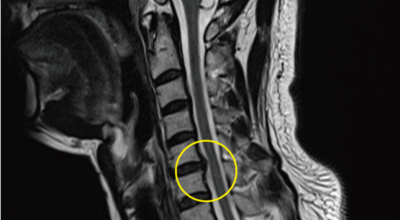

경추 사이의 추간판(디스크)이 탈출 또는 파열되어 경추신경이 자극이나 압박을 받아 통증이 생기는 증상을 말해요. 경추는 운동성이 큰 부위로 추간판이 압력을 받으면 튀어나와 척수나 신경을 압박하게 되는데요 목디스크는 퇴행성 변화 이후에 발생되기 때문에 많은 환자들이 만성적인 통증을 지니고 있는 경우가 많습니다.

디스크의 수핵이 빠져나가거나 퇴행성 경추 척추증 또는 경추관협착증 등으로 척수가 눌리게되면 대부분이적으로는 팔의 힘이 빠지는 느낌을 받을 수 있답니다. 척수가 눌린 정도에 따라서는 한쪽 팔만 마비되기도 해요. 하지만 양쪽 팔의 감각이 둔해지고 눈을 감으면 무질서하게 되는 경우도 있어서 이러한 목디스크 증상이 나타나면 매우 위험한 상태이니 빠른 치료가 필요해요.

비수술적 치료가 효과가 없다거나 디스크의 신경압박이 극심한 경우엔 시술할 관조차 들어갈 공간이 없으므로 비수술을 할 경우 주변의 정상조직까지 훼손이 될 위험이 있어요. 미세 현미경 수술이나 인공 디스크 치환술 또는 경추유합술을 통하여 치료가 할 수 있는데 가능하다면 비수술치료가 권장되지만 정확한 진단이 우선되어야 하므로 자세한 사항은 전문의와 상담하여 결정하는 것이 좋습니다.